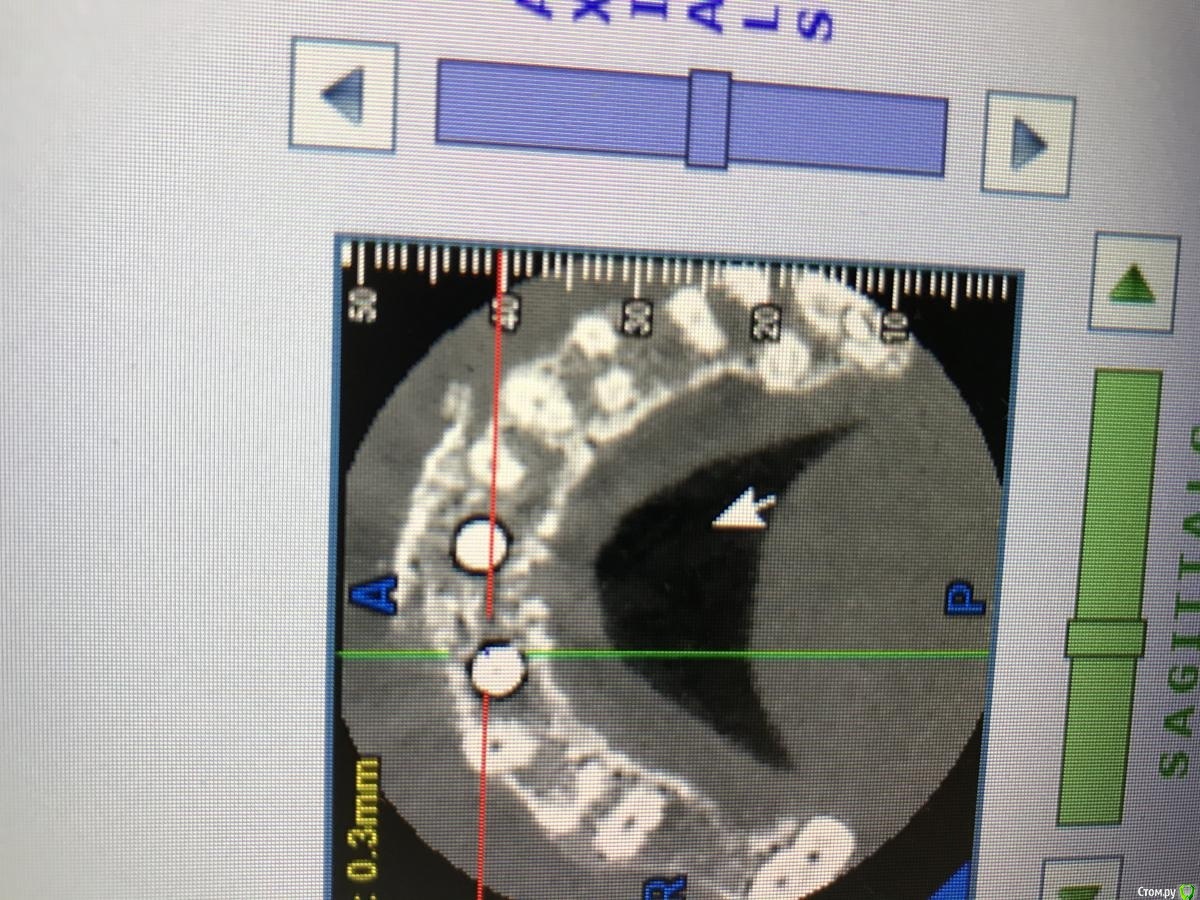

MakovskyAlexandr Опубликовано 8 октября, 2020 Поделиться Опубликовано 8 октября, 2020 Здравствуйте, люди добрые, подскажите пожалуйста.Удалены 2 Корня(21 и 12). Пациентка отказалась от трёх коронок, изъявила желание именно двумя восстановить.Удалены корни - установлены импланты анкилоз А3.5 11 и 14 мм.Выполнена костная пластика , материал ограждён мембраной- все по классике, мембрана фиксирована пинами. Я так понимаю произошло смещение материала( то от гематома, то ли отёк такой). Как быть дальше? Ждать интеграции и подсаживать потом аутотрансплантат?Спасибо огромное. Ссылка на комментарий

колесников Опубликовано 8 октября, 2020 Поделиться Опубликовано 8 октября, 2020 Анкилос надо было топить хорошо и грузить. Мне кажется или для 11 нет места? 1 Ссылка на комментарий

MakovskyAlexandr Опубликовано 8 октября, 2020 Автор Поделиться Опубликовано 8 октября, 2020 Анкилос надо было топить хорошо и грузить. Мне кажется или для 11 нет места?Для 11 нет места. Ссылка на комментарий